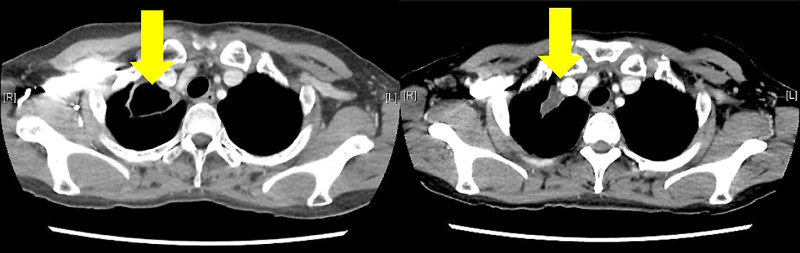

陳女士是補教老師,長期咳嗽超過半年,起初以為只是普通感冒,嘗試中藥與民間偏方皆未改善,不僅咳出大量濃痰,體重還驟降5公斤,一度懷疑罹患肺癌。經外院檢查,痰液細菌培養呈現「分枝桿菌」陽性,依肺結核進行治療後仍未好轉,轉診本院,安排支氣管鏡與多次痰液細菌培養檢驗,最終確診為非結核分枝桿菌-「膿腫分枝桿菌」感染。

由於陳女士工作繁忙,無法長期住院接受注射治療,改採口服抗生素搭配居家型霧化吸入抗生素,同時由呼吸治療師指導霧化器的正確使用方式,以確保藥效發揮,經過一年的治療與定期追蹤,痰液檢驗轉為陰性,肺部病灶明顯縮小,生活品質明顯改善。